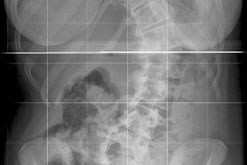

Curvature of the spine that predominantly affects girls.

When she was eleven years old Erika Maude’s parents noticed that she suffered from curvature of the spine. Scoliosis was eventually diagnosed and she was fitted with a back brace. When she was fifteen she went to Barcelona to have special physiotherapy-based treatment in 2002. She says the improvement was dramatic, and after returning to Britain she set up her own clinic. The treatment is called the ‘Katharina Schroth Method’. In Britain it is only available privately and many surgeons question its credibility. Jenni is joined by Erika and by Brad Williamson, President of the British Scoliosis Society and a Consultant in Spinal Surgery.